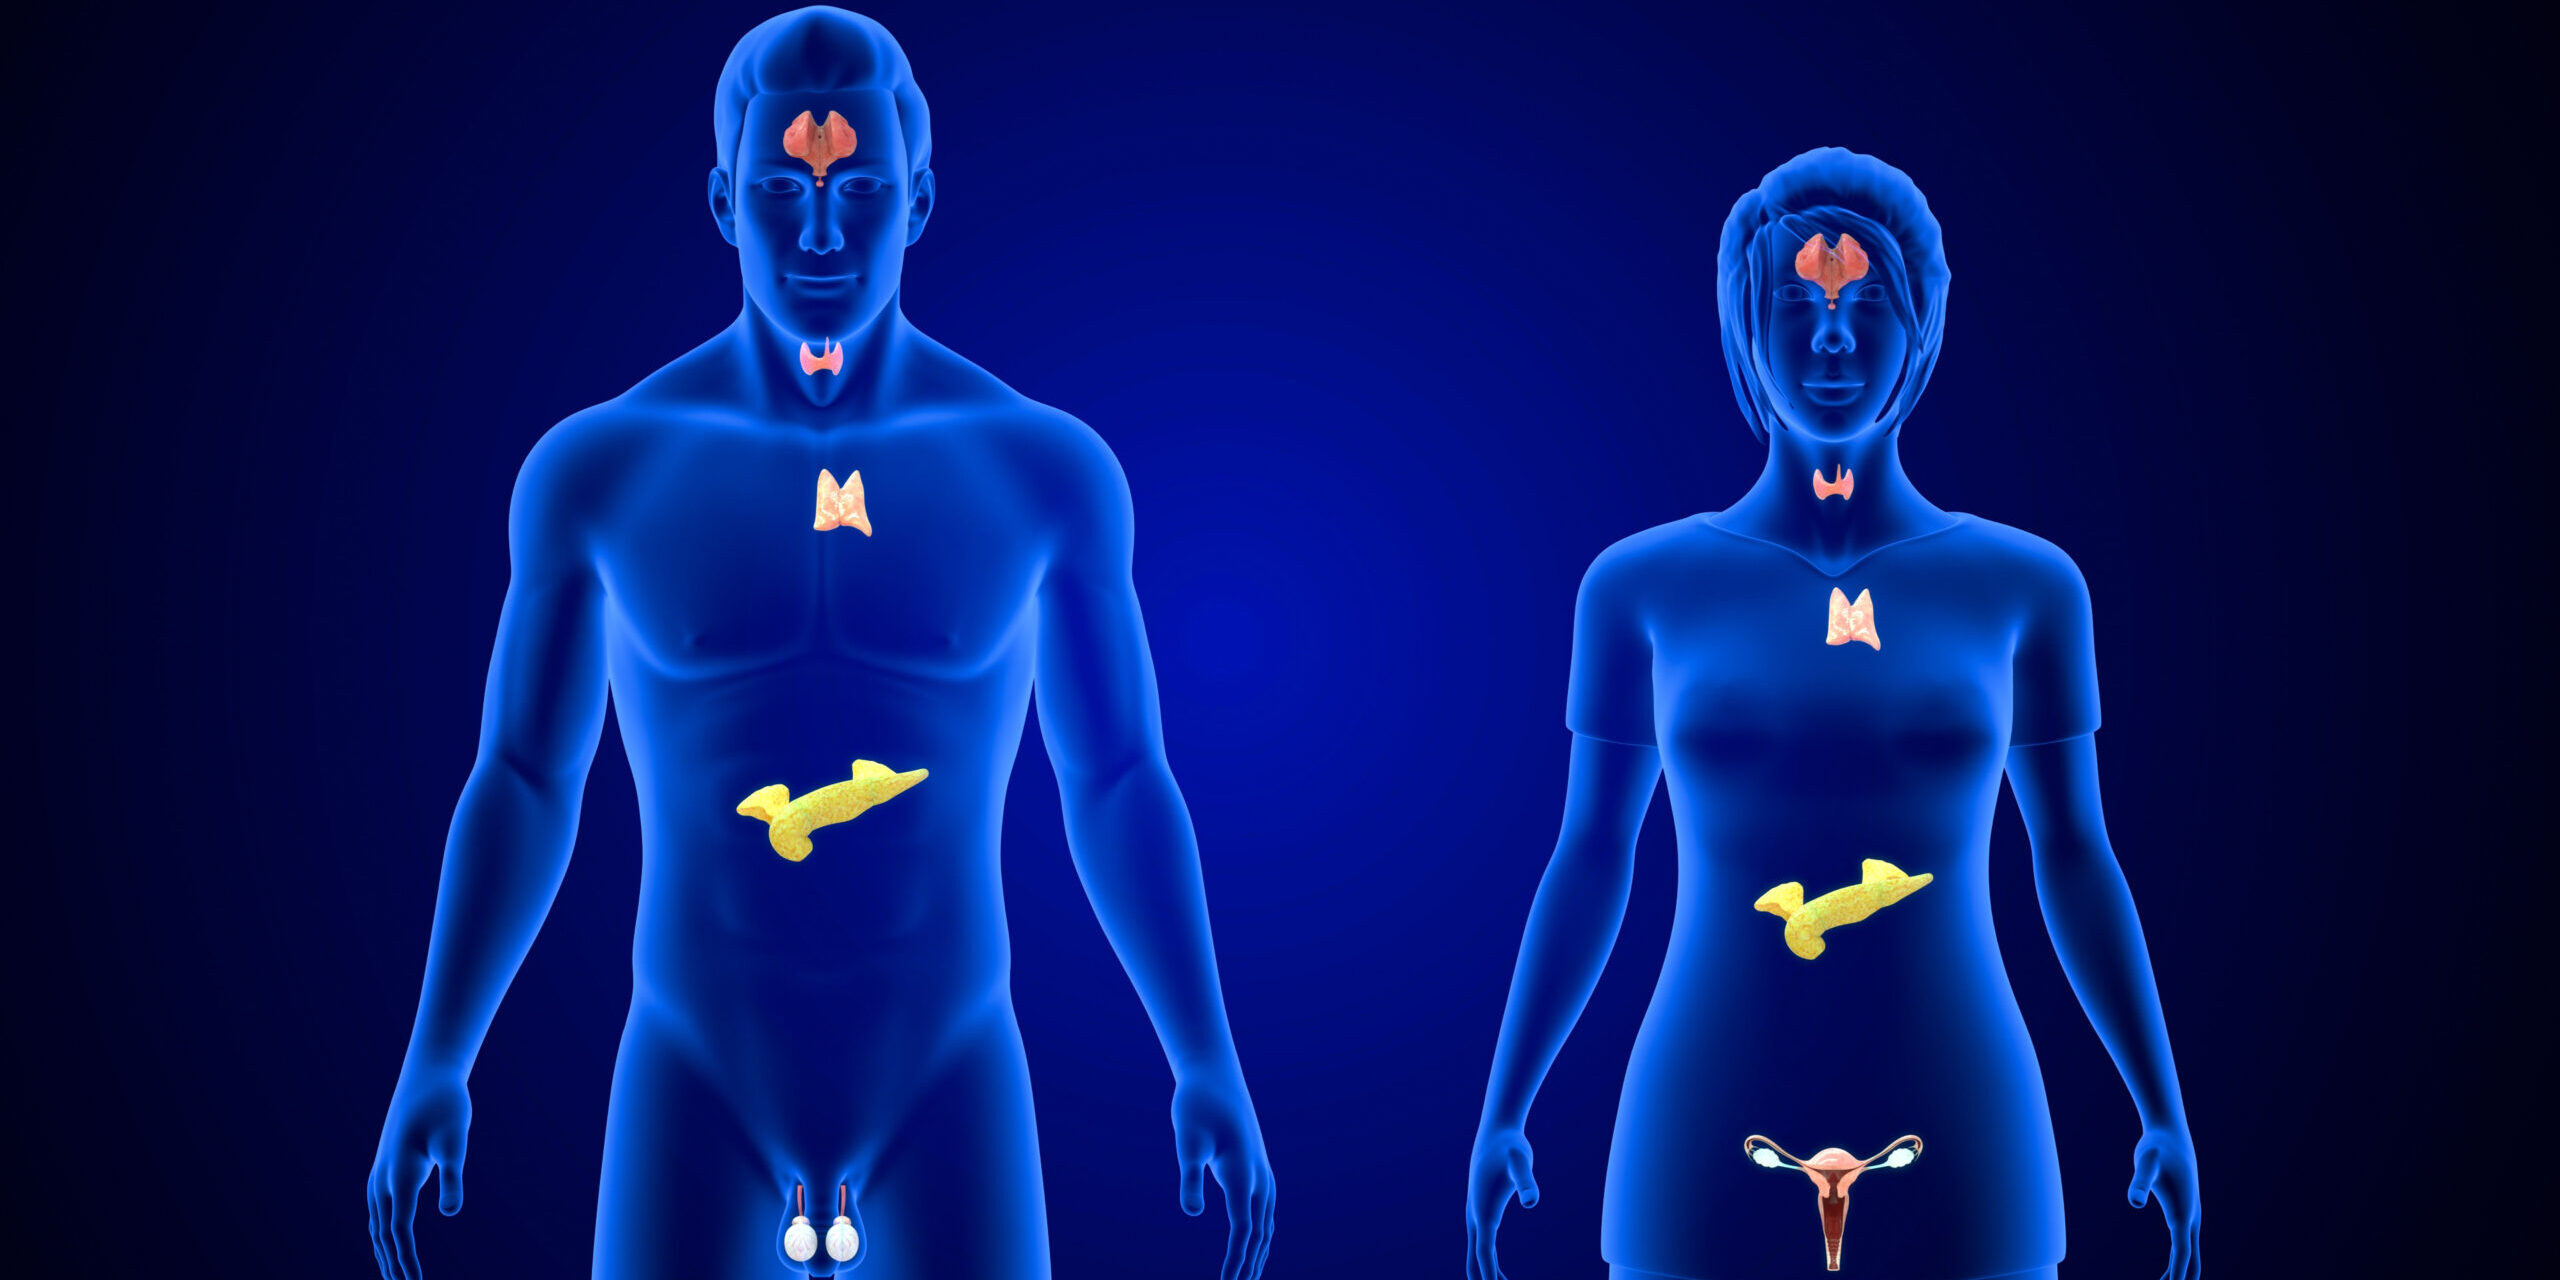

We co-ordinate expert surgical oncology with wholistic multidisciplinary management. From the first consultation to your recovery, we're with you for every step - so you can focus on what matters most: living your life fully and confidently.

Our specialists focus on complex oncological surgeries. Treating you with skill, understanding and compassion before, during and after surgery.

Multidisciplinary Care

Fully integrated cancer care, collaborating with top specialists across Sydney, New South Wales, and beyond.